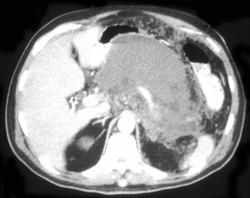

Pancreatic Cancer Encases PV/SMV With Collaterals